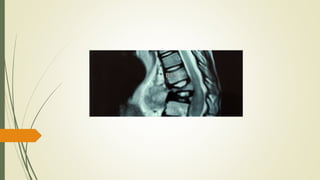

MRI Spine

• 37.